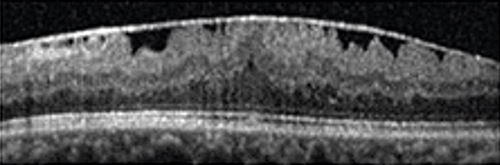

• OCT (tomografia a coerenza ottica) : è l’esame fondamentale per confermare la diagnosi e valutarne la gravità. Permette di analizzare gli strati retinici attraverso una sorta di “TAC” a raggi infrarossi (quindi non invasiva).